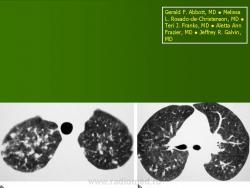

Изучение скелетограмм у 27 из 29 больных позволило выявить изменения, подтвердившие диагноз данного заболевания. Это указывает на высокую диагностическую ценность рентгенологического обследования при ГКЛ. Наиболее часто определялись поражения черепа в виде множественных (24) или единичных (3) дефектов в костях свода, где четко прослеживалась «штампованность» очагов. Дефекты не содержали секвестров, имели различную форму, величину, четкие наружные и неровные, фестончатые внутренние контуры. Периостальная реакция отсутствовала. При множественных участках деструкций картина напоминала «географический или ландкартообразный» череп, или «изъеденную молью ткань» (Рис.1).

Кости чаще поражаются у детей старшего возраста. В зависимости от локализации поражения, наблюдаются симптомы «экзофтальма», «гнойного отита», «гипертрофического гингивита», патологические переломы в области деструкции, компрессия тел позвонков. При рентгенологическом исследовании выявляются литические очаги с отчетливыми контурами (рис. 20).

Рис. 1. Боковая краниограмма, больной Б. С., 3 года. Множественные литические очаги деструкции в костях черепа.